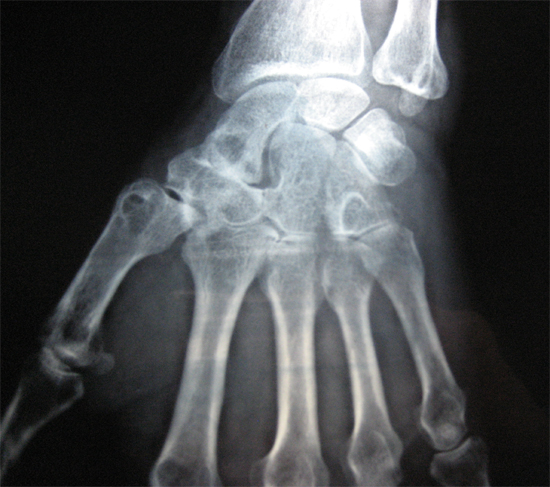

Cas clinique N°43

Dr Véra Lemaire Paris

Il s'agit d'un patient âgé de 72 ans qui a fait une chute sur le poignet. Une radiographie a été faite.

Lors de la consultation, il ne s'en plaint pas.

Qu'en pensez-vous ?